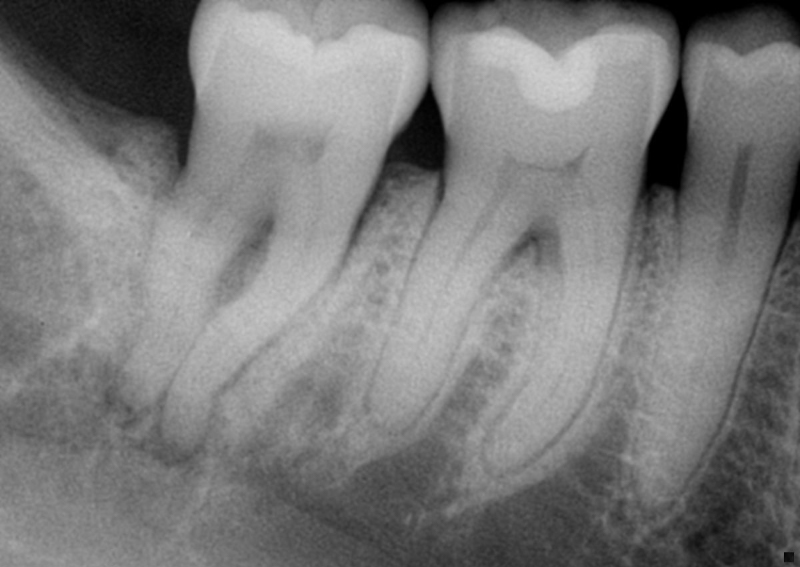

This is known as “fracture necrosis.” Figures 1A-1C highlight an undiagnosed root fracture in the lower second molar. Note non-vital pulp with periapical/periradicular bone loss and no restoration or caries. The clinician should question why the pulp became non-vital. With no other objective etiology, a vertical root fracture should be considered.

Radiographs and especially CBCT are valuable diagnostic tools for determining the presence of a root fracture. Unfortunately, unless the fracture is wider than about 0.15 mm (the tip of a #15 endodontic file), it cannot be visualized in the CBCT scan. There are some strong associations between radiographic findings and the presence of a root fracture. Specifically, when the bone loss presents in a “J” shaped pattern, it is highly suggestive that a root fracture is present.

This can often be seen on a two-dimensional periapical radiograph, with the bony lesion typically extending from the apex to the crestal bone, sometimes resulting in a deep and narrow isolated periodontal pocket. This pocket sometimes cannot be probed because it occurs in the interproximal area. Taking radiographs of the lower second molars can be challenging, especially with patient compliance (sometimes the tooth is “way back there” and may be uncomfortable for the patient).